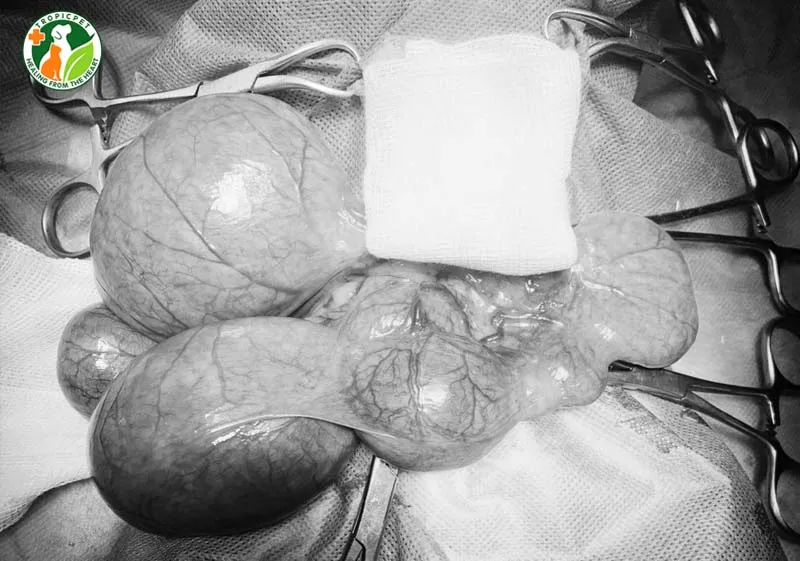

Phẫu thuật cắt bỏ toàn bộ tử cung và buồng trứng là phương pháp điều trị hiệu quả nhất hiện nay. Quy trình này giúp loại bỏ hoàn toàn nguồn gốc gây nhiễm trùng và ngăn ngừa bệnh tái phát.

Trước khi phẫu thuật, chó cần được truyền dịch để ổn định huyết áp và hỗ trợ chức năng thận. Các loại kháng sinh phổ rộng liều cao sẽ được tiêm tĩnh mạch để kiểm soát sự lây lan vi khuẩn.

Bác sĩ phẫu thuật sẽ tiến hành rạch một đường ở đường trắng giữa bụng để tiếp cận cơ quan sinh sản. Tử cung lúc này thường rất mỏng manh và dễ vỡ nên thao tác đòi hỏi sự khéo léo cực cao.

Sau khi cắt bỏ tử cung, bác sĩ sẽ kiểm tra kỹ ổ bụng để đảm bảo không có dịch mủ rò rỉ. Vết thương được khâu lại bằng các mũi khâu thẩm mỹ và đảm bảo độ bền chắc trong quá trình hồi phục.

Phẫu thuật trong tình trạng viêm nhiễm nặng luôn tiềm ẩn rủi ro cao hơn so với triệt sản thông thường. Tuy nhiên, đây là cơ hội tốt nhất để cứu sống chú chó bị viêm tử cung đang trong cơn nguy kịch.

Chó cần được lưu lại bệnh viện từ 2 đến 4 ngày để theo dõi sát sao các chỉ số sinh tồn. Việc chăm sóc hậu phẫu chuyên nghiệp giúp ngăn ngừa các biến chứng như nhiễm trùng vết mổ hoặc bục chỉ.

Sau phẫu thuật, chó sẽ không còn khả năng sinh sản nhưng sức khỏe tổng thể sẽ được cải thiện rõ rệt. Đa số chó cái sẽ phục hồi hoàn toàn nếu ca phẫu thuật được thực hiện trước khi tử cung bị vỡ.